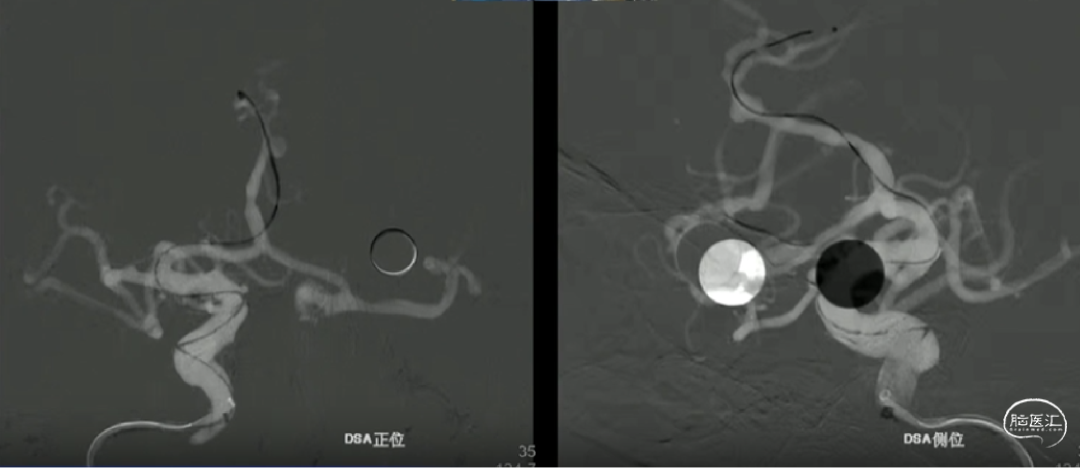

如意中段释放

心玮“如意”血流导向密网支架相较于其他钴铬合金材质,密网支架略软,释放远端动脉瘤不会影响血管的走形。

中段释放后,造影,动脉瘤滞留明显,支架贴壁打开良好,支架位置合适。